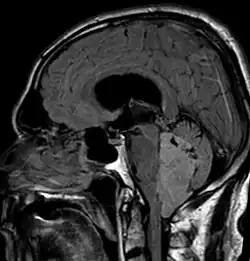

Ependymoma of 4.ventricle in MRI. -